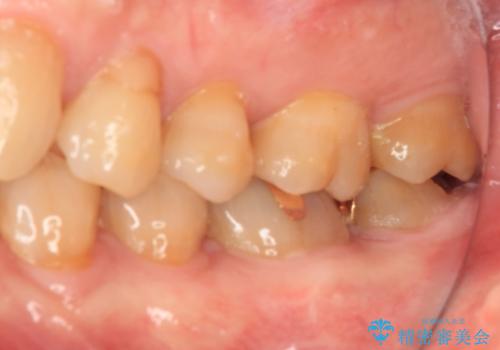

1番奥の歯はゴールドインレー周りがむし歯で欠けており、手前の歯はインレーの下にむし歯がある状態でした。

1番奥は歯肉に覆われている部分が大きいため、欠損部とむし歯の部分をゴールドインレーにて修復し、手前の歯はオールセラミッククラウンにて補綴治療を行うこととしました。